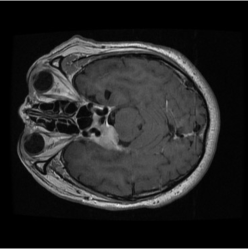

Numerous coreset selection works (Huang et al., 2023; Loshchilov and Hutter, 2015; Marion et al., 2023; Park et al., 2024; Paul et al., 2022; Xia et al., 2022; Yang et al., 2023a) have explored various criteria for identifying important data samples, including geometry distance (Sener and Savarese, 2017; Welling, 2009), uncertainty (Coleman et al., 2019), loss (Toneva et al., 2018; Paul et al., 2021), decision boundary (Ducoffe and Precioso, 2018; Margatina et al., 2021), and gradient matching (Mirzasoleiman et al., 2020). However, most of these methods have been validated mainly on natural image datasets, such as CIFAR-10, CIFAR-100 (Krizhevsky et al., 2009), and not extensively on medical datasets. The applicability of those methods for medical image datasets are under exploration, given the unique characteristics of medical images. Compared to natural image datasets, the intra-class variation and inter-class similarity of medical image datasets (Song et al., 2015) pose specific challenges to coreset selection. On the one hand, in medical imaging, samples within the same category can exhibit significant differences, making it difficult to capture consistent features for each class. This variation largely comes from the diversity in disease manifestation across patients and discrepancies in imaging conditions. On the other hand, the challenge of inter-class similarity arises when images representing different diseases exhibit similar visual characteristics. fig. 6 provides a more straightforward demonstration of this characteristic. These factors contribute to the complexity of medical image analysis and underscore the need for sophisticated coreset selection methods that can effectively address these challenges.

Despite the substantial progress, integrating deep learning into medical imaging is fraught with challenges (Ker et al., 2017). The effectiveness of DL in this context is largely dependent on the availability of large, well-annotated datasets tailored for specific tasks and reliant on advances in high-performance computing. The necessity for vast complex datasets introduces complications such as inconsistencies in data quality, arising from variations in imaging equipment and protocols. Moreover, the extensive volume of medical data demands significant computational resources, posing logistical challenges for efficient processing (Zhou et al., 2021). Additionally, the inherent heterogeneity of medical images, characterized by a multimodal probability distribution, complicates the model training process by requiring algorithms capable of handling diverse visual features and patterns within the data. Another issue is the inter-class similarity and intra-class variation, as depicted in fig. 6, where different diseases may appear similar, and the same disease may present differently across patients.